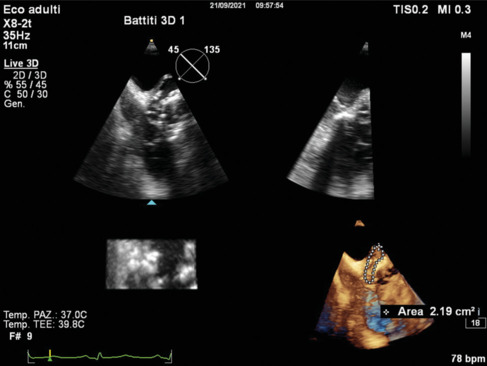

Abstract Image